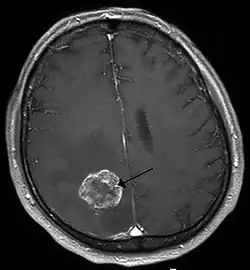

Medical conditions

Brain tumors are among many medical conditions in which seizures can be a symptom